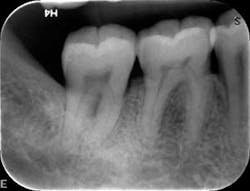

At nine months, the patient’s tissues appeared pink with no inflammation. Radiographs revealed new bone growth, especially around teeth Nos. 3, 15, and 31 (figures 10–12). The patient reported his HbA1c level stable at 8.2.

Radiographs nine months after LANAP treatment (figures 10–12)